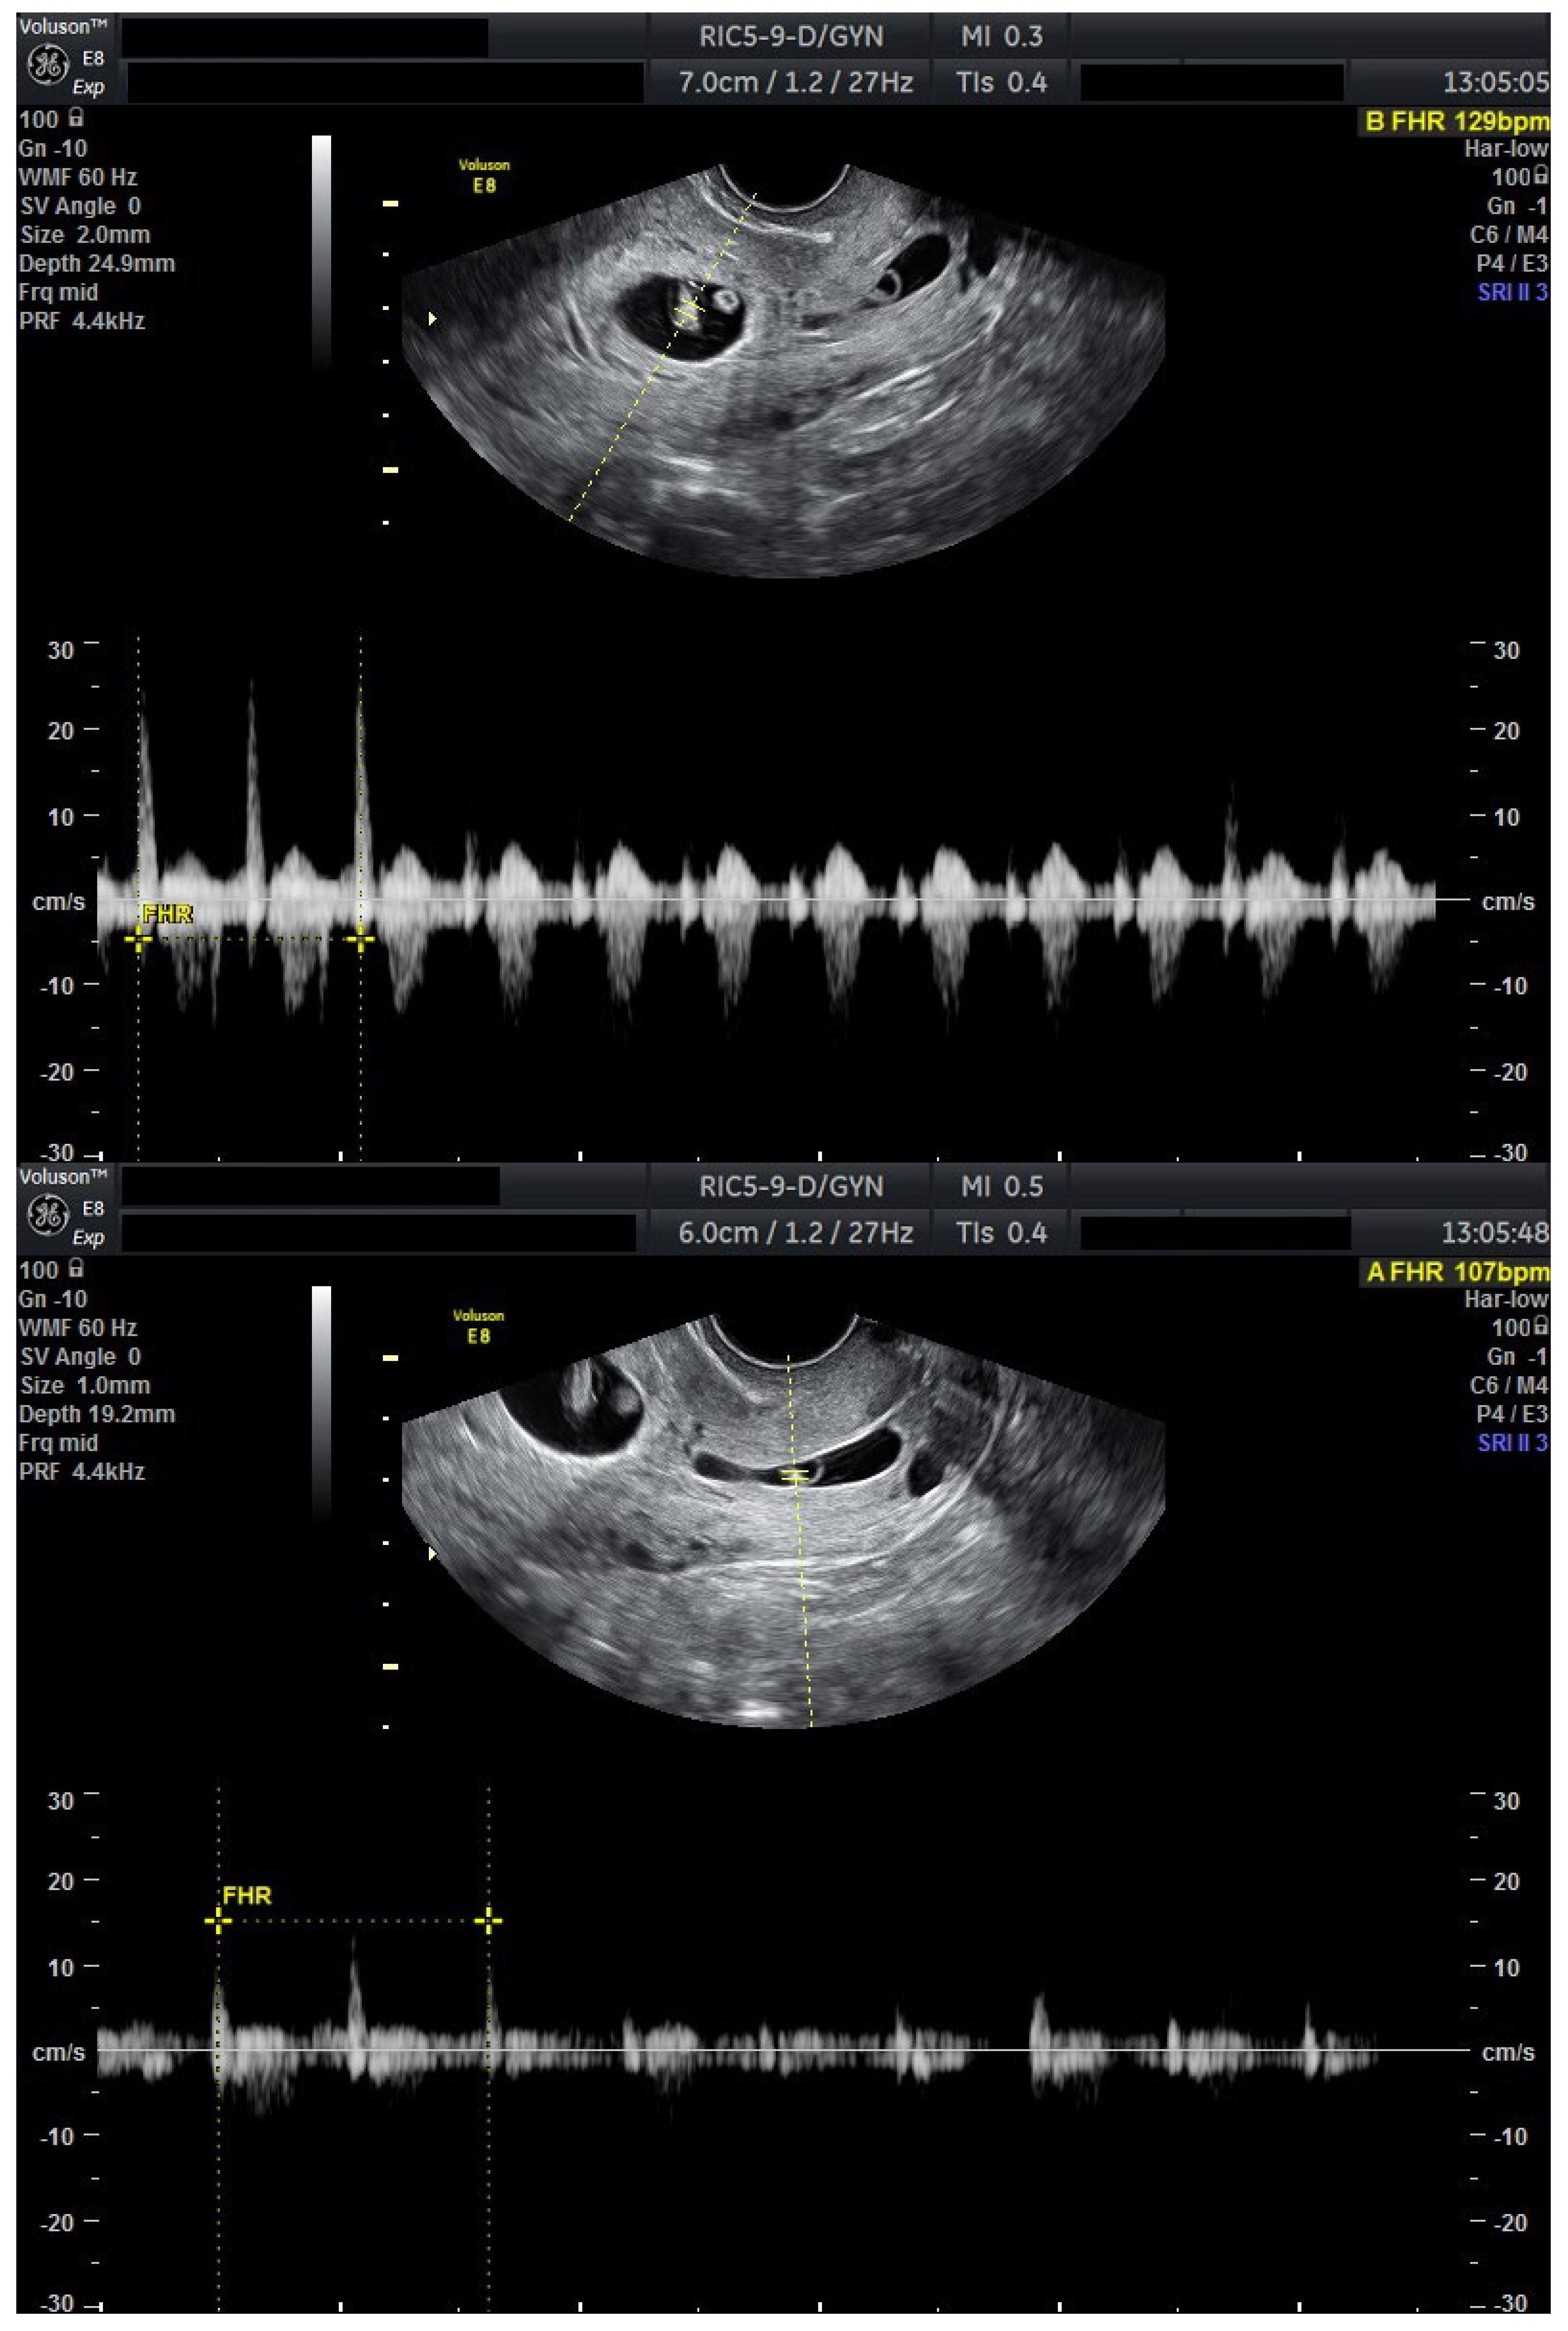

We present a personal case from our tertiary center in western Romania as an example of applicable findings from this review. A 32-year-old woman presented to the Municipal Clinical Emergency Hospital of Timișoara with first-trimester vaginal bleeding. Transvaginal ultrasound revealed a viable intrauterine gestation with a seven-week-old embryo with positive cardiac activity, as well as a simultaneous viable CP, confirming the diagnosis of HCP (Figure 1).

Figure 1.

Ultrasound evaluation at diagnosis with viable heterotopic embryos (Day 0). Combined ultrasound of both gestational sacs. Transvaginal ultrasound evaluation: sagittal view through the uterus and cervical canal. FHR present in both embryos. Patient information is anonymized.

The patient first received mifepristone 200 mg orally at time of diagnosis (Day 0). At 48 h, repeat ultrasound demonstrated persistent cardiac activity in both the intrauterine and cervical gestations.

A second, higher dose of mifepristone 600 mg was then administered at this time (Day 2). Another 48 h later (Day 4), the CP no longer demonstrated cardiac activity, whereas the intrauterine pregnancy remained viable, but severely bradycardic (FHR = 67 bpm).

To ensure complete trophoblastic regression in both pregnancies, systemic methotrexate 100 mg was administered intramuscularly at this time (Day 4). A follow-up ultrasound at 48 h (Day 6) confirmed the absence of cardiac activity in both gestations, disorganized gestational sacs, consistent with successful termination. Cervical stromal vascularity identified on color Doppler was suggestive for trophoblastic remnants (Figure 2).

Figure 2.

Ultrasound results after methotrexate 100 mg (Day 6). Transvaginal ultrasound evaluation: both sagittal view through the uterus and transverse view through the cervical canal. A total of 48 h after methotrexate 100 mg (Day 6): both embryos without cardiac activity. Cervical stroma with vascularity. Patient information is anonymized.